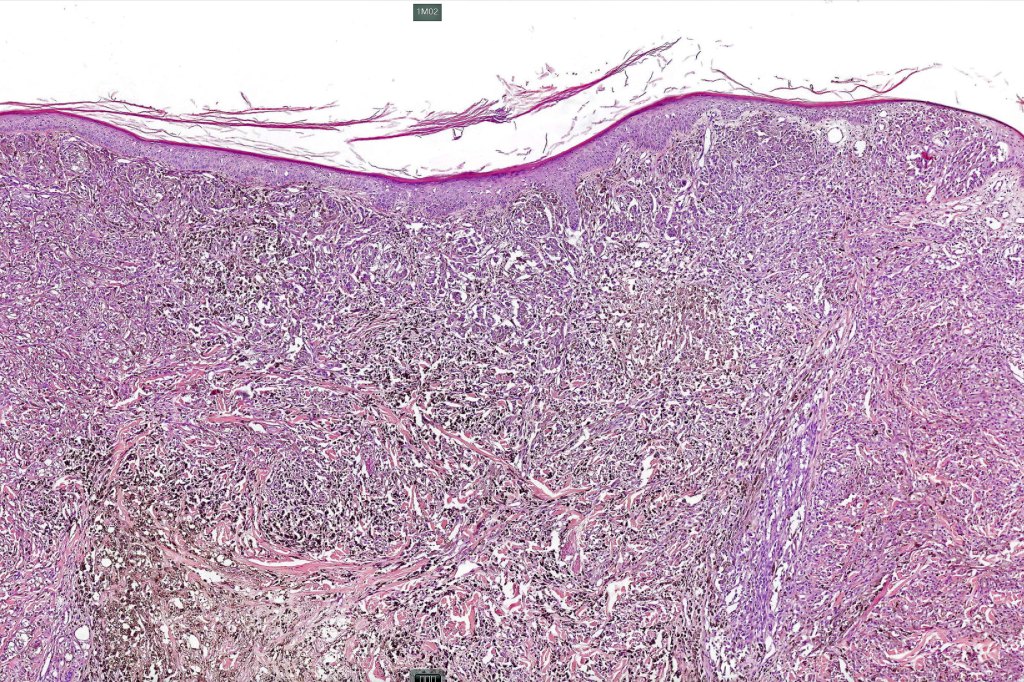

Histological features

•Develops within a precursor lesion as one or more nodules of epithelioid or spindled cell melanoma

•Or melanoma showing admixed blue nevus-like features (dendritic cells and melanophages) in the absence of a precursor lesion

•The latter may show a dumbbell appearance at low power or scanning magnification